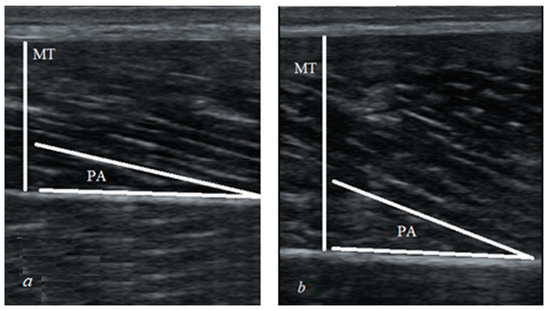

| MT (mm) | 17.2 ± 3.5 |

| PA (°) | 10.6 ± 1.9 |

| FL (mm) | 94.7 ± 16.5 |